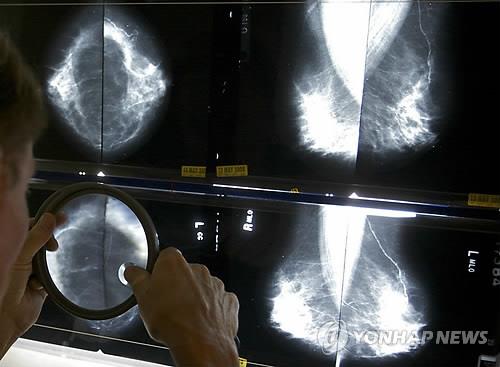

항암치료 유방암 여성, 지문 사라져

(서울=연합뉴스) 한성간 기자 = 유방암 환자가 항암치료 부작용으로 지문이 사라진 희귀한 사례가 발생했다.

멕시코 의과학·영양학연구소의 야닌 차바리-게라 박사는 암세포가 폐로 전이돼 항암화학요법을 받던 65세의 진행성 유방암 환자가 지문이 지워졌다고 밝힌 것으로 헬스데이 뉴스가 15일 보도했다.